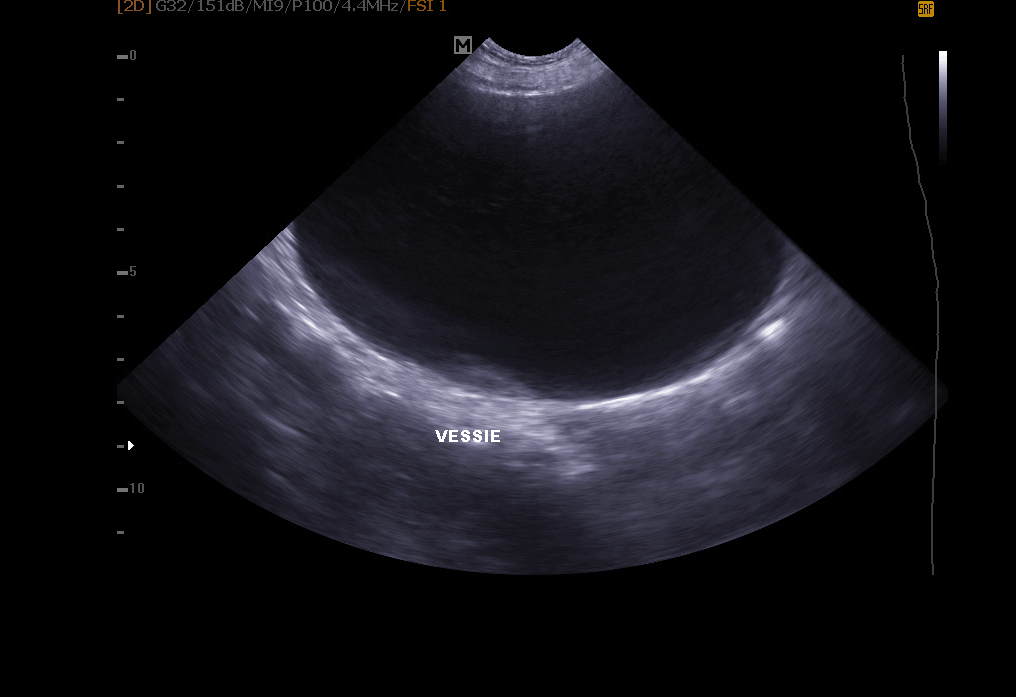

Echographie abdominale: elle permet l’exploration de le vessie (recherche de calculs, polypes, tumeur), des reins, de la rate , du foie , du pancréas et autres organes abdominaux.